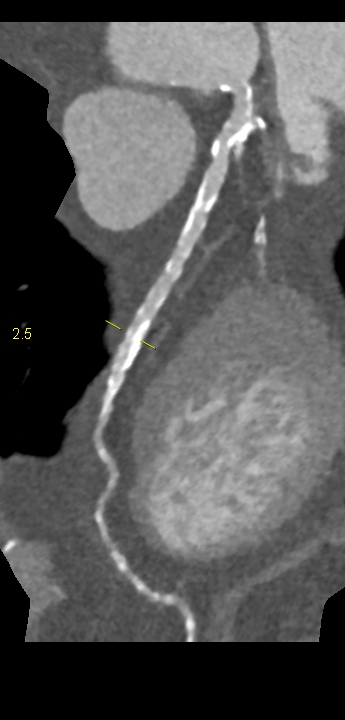

Figura 3: reconstrucție “în lungul vasului” artera circumflexă din achiziția angiocoroCT